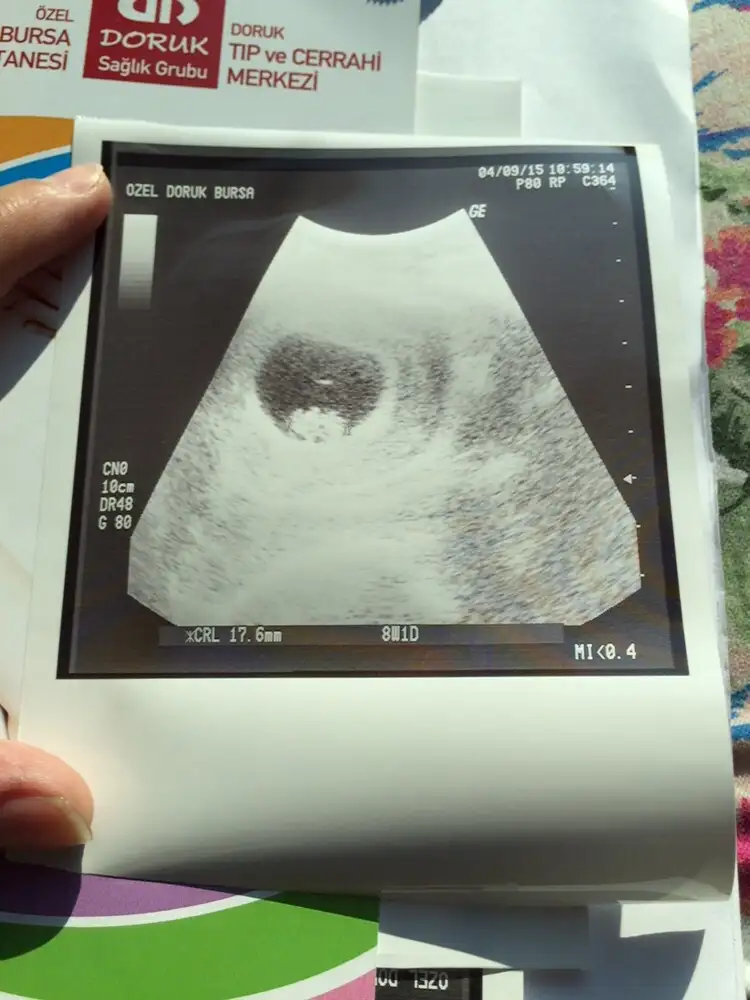

Kızlar merhaba daha çok küçük 8 haftalık ama bişey anlayan varmı çok merak ediyorum cinsiyetini :)

Eklentiler

• image.webp

image.webp

17,4 KB · Görüntüleme: 235

Kese epilepsi seklinde ve bozuk erkek olabilir canim kendini fazla kaptirma burdaki teorilere gore konuşuyorum. Bütün teoriler kiz diyor benimkine icimde hâlâ erkek olacak hissi var merak cok kotu bisey ya geceleri ruyama bile giriyor poof :(

Cnm seninkide erkek sanki,ORKD arkadaşımızın dediği çizgi şeklindeyse erkekmiş.senin bebisde öyle duruyor.

Ay yok canim benim kese yuvarlak olursa kiz epilepsi yani sekli bozuk olursa kiz dediler bi msj da ondan oyle dedim bebek çizgi seklindeyse erkek mercimek gibi yuvarlaksa kiz diyende oldu.